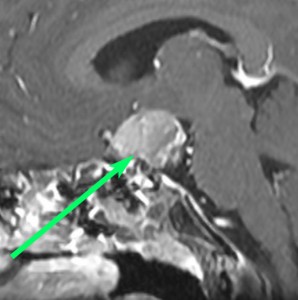

8歳で両側の視力低下が生じました。眼科では精神的なものと診断されて,4ヶ月くらいで右視力 0.4(耳側半盲),左指数弁となりました。のう胞性頭蓋咽頭腫で大きな骨化を伴うもので1月くらいの間に全盲になるかもと判断しました(失明寸前です)。

矢印の先に見えるように下垂体は正常の形態です。この画像から灰白隆起の左後方,乳頭体の前方が腫瘍発生母地ということがわかります。尿崩症もなく下垂体機能は正常です。経鼻的な内視鏡手術で腫瘍の大部分を摘出すれば下垂体機能は廃絶します。

とにかく失明を避けるために急いで経蝶形骨洞手術(transsphenoidal-transtuberculum sellae approach)で腫瘍のう胞の減圧をしました(緑の矢印の経路 by 函館中央病院加藤功先生)。その後に前頭開頭で腫瘍を全摘出しました(右側の画像)。尿崩症はでましたが下垂体前葉機能は正常です。

右視力 0.45,左明暗弁の視力が残りました。でももし,経鼻手術をしないでいきなり開頭すればおそらく全盲になっていた例です。